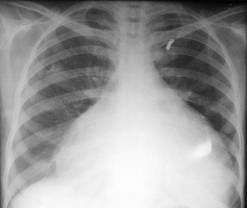

INSUFICIENŢA AORTICĂ

- largirea pedicolului vascular prin dilatarea aortei ascendente si accentuarea importanta a butonului aortic

marirea arcului inferior stâng prin hipertrofia si dilatarea ventricolului stâng

adâncirea arcului mijlociu

La examenul radioscopic, se evidentiaza pulsatii ample la nivelul arcului inferior stâng, a aortei ascendente si butonului aortic.